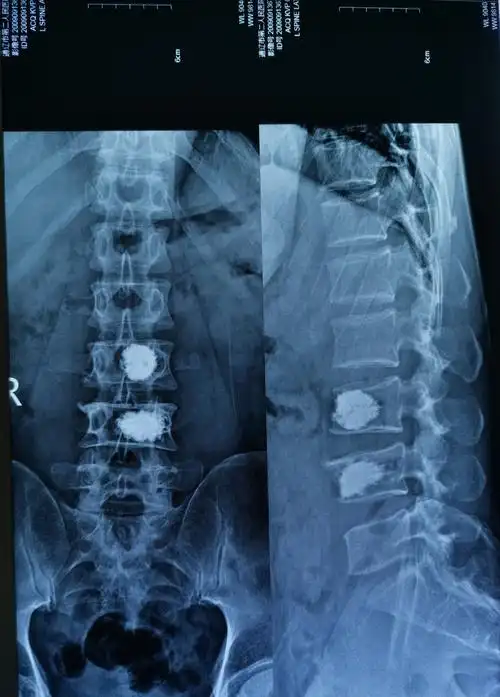

44岁腰椎3,4椎体压缩性骨折椎体成型手术一例